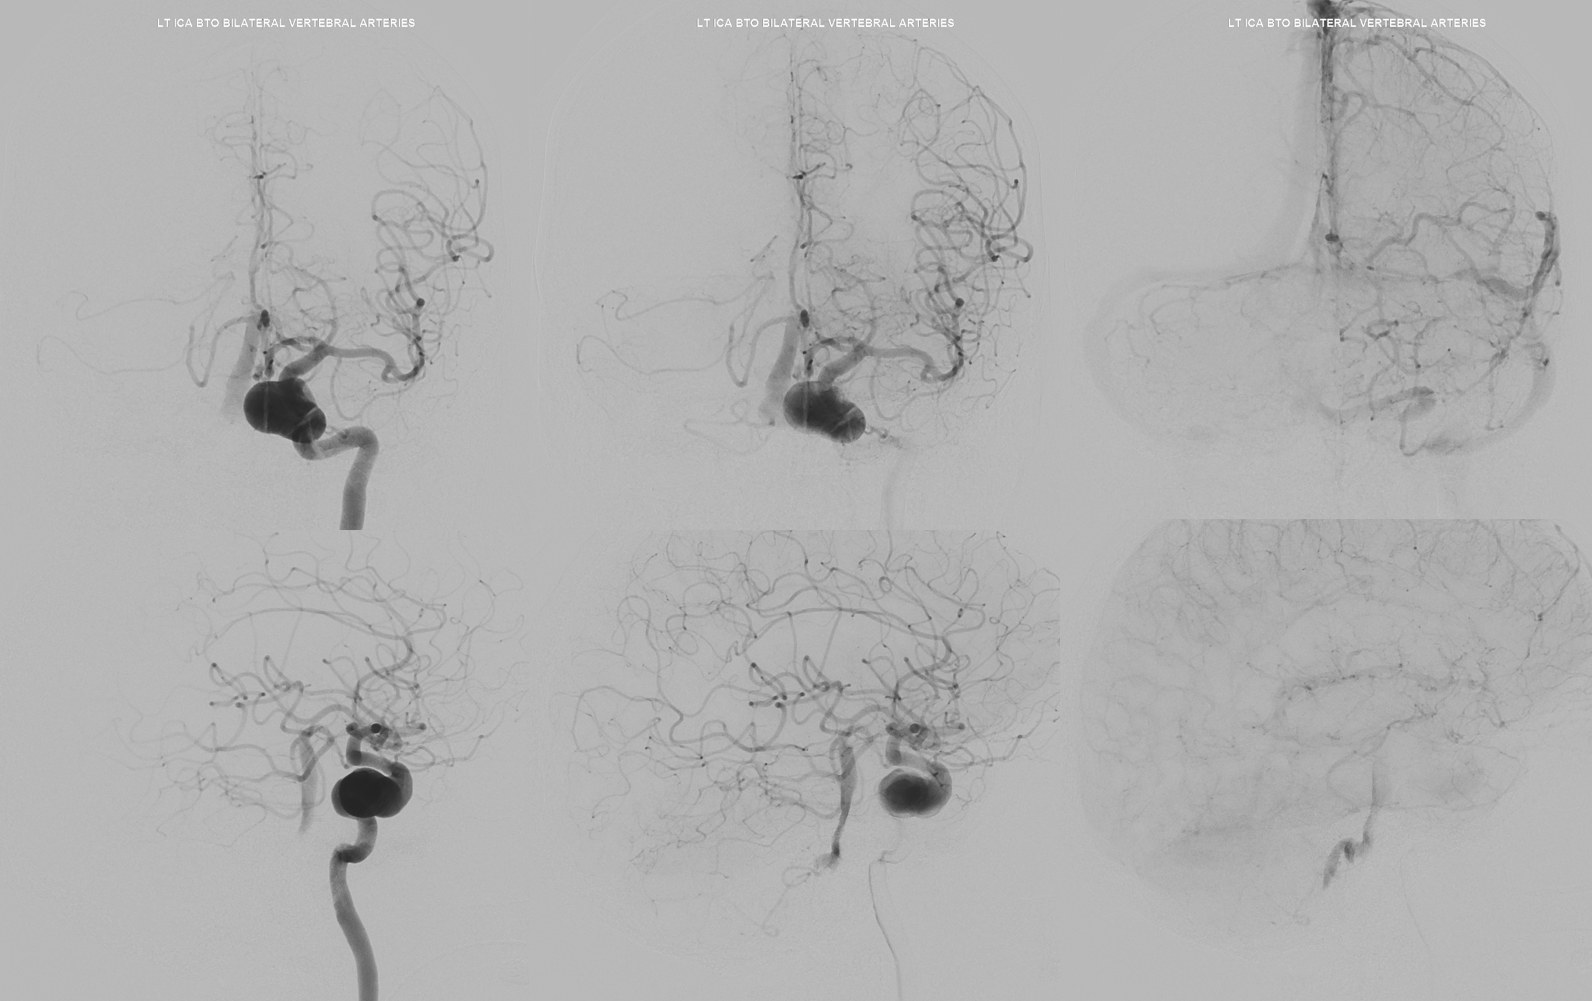

Now for the BTO — need 3 access points — two femoral one radial. Block 2 verts (essential) and inject ICAs sequentially

BTO